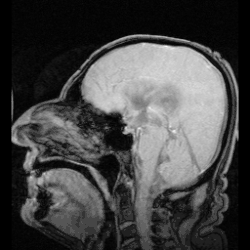

![]() The cerebrospinal fluid circulates in the subarachnoid space around the brain and spinal cord, and in the ventricles of the brain. | |

CSF occupies the subarachnoid space (between the arachnoid mater and the pia mater) and the ventricular system around and inside the brain and spinal cord. It fills the ventricles of the brain, cisterns, and sulci, as well as the central canal of the spinal cord. There is also a connection from the subarachnoid space to the bony labyrinth of the inner ear via the perilymphatic duct where the perilymph is continuous with the cerebrospinal fluid. The ependymal cells of the choroid plexus have multiple motile cilia on their apical surfaces that beat to move the CSF through the ventricles.

In humans, there is about 125–150 mL of CSF at any one time.[3] This CSF circulates within the ventricular system of the brain. The ventricles are a series of cavities filled with CSF. The majority of CSF is produced from within the two lateral ventricles. From here, CSF passes through the interventricular foramina to the third ventricle, then the cerebral aqueduct to the fourth ventricle. From the fourth ventricle, the fluid passes into the subarachnoid space through four openings – the central canal of the spinal cord, the median aperture, and the two lateral apertures.[3] CSF is present within the subarachnoid space, which covers the brain and spinal cord, and stretches below the end of the spinal cord to the sacrum.[3][4] There is a connection from the subarachnoid space to the bony labyrinth of the inner ear making the cerebrospinal fluid continuous with the perilymph in 93% of people.[5]